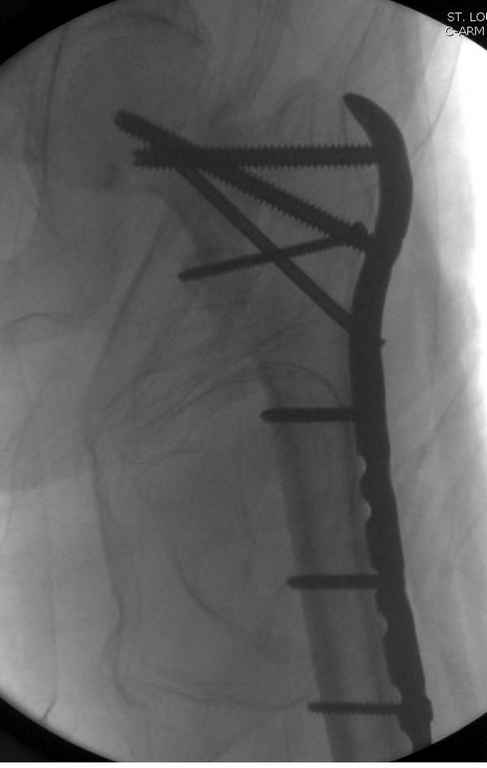

Здесь пара похожих случаев.

St. Louis University Medical Center

Увожаемый коллега,мое мнение:фиксация и\медул.блок. стержнем Gamma-long "STRYKER". Вероятно, закрыто сделать полностью может не получится. Откроетесь на 6-8 см. для репозиции промежуточного фрагмента, но только после установки стержня. Удачи!!!